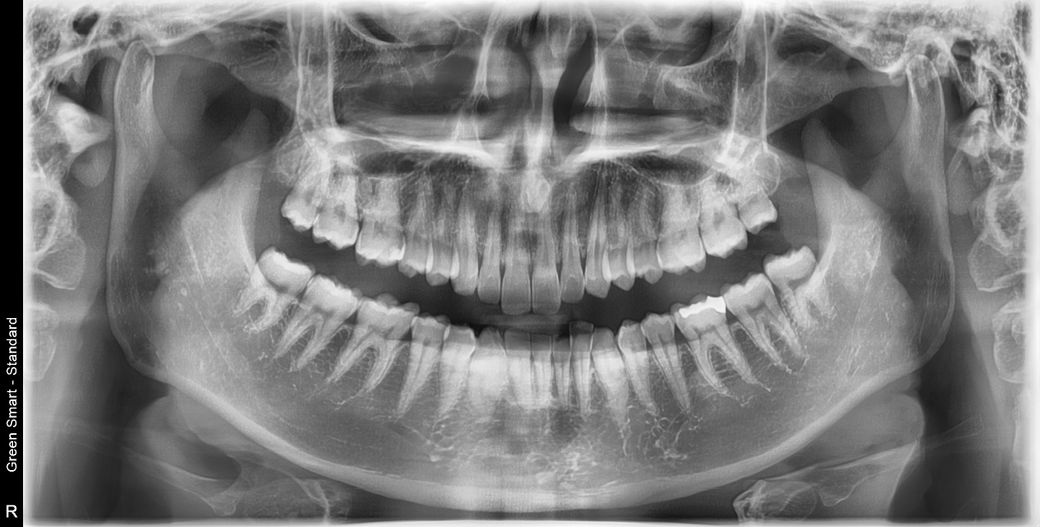

한 2주 전부터 왼쪽턱에서 딱 소리가 난 후 입을 크게 벌리거나 어느쪽이던 질긴 음식(예: 건새우, 나물 등)을 씹으면 5-7정도의 통증이 있어요. 병원에서 약 받고 물리치료도 받고 있는데, 사랑니가 근본적인 원인인거 같다고 발치를 권유받았는데 그럴 수 있나요? 사랑니 발치 후 회복기간도 그렇고, 발치 후 문제가 생기지는 않을까 걱정이 됩니다. (사진처럼 사랑니가 위치는 잘 난편인데 어금니를 깨물때 양쪽다 동시에 맞물리지는 않고 한쪽만 맞물립니다, 사랑니는 잘 나왔어도 빼는게 좋은편인가요? )

• 1번 째 사진

현재로선 특별히 사랑니가 턱관절 통증에 기여요인이 될 정도로 삐뚤게 나오거나 어디를 자극하고 있지는 않습니다. 발치를 원하지 않는다면 턱관절 물리치료, 약처방 등의 치료를 좀 더 받아보시는 것도 좋을 것 같습니다. 현재 사랑니 맹출 양상으로만 따지자면 발치가 불필요합니다.